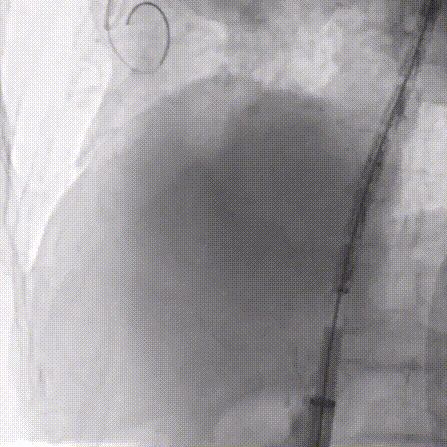

6.再送入Pigtail导管胸主动脉造影:主动脉弓见一巨大瘤样突出,降主动脉见2处瘤样扩张,与CT一致。

7.更换GORE® DrySeal亲水涂层导引鞘 DSF2233,送入唯强胸主动脉覆膜支架(DM-TC-3024200)至主动脉弓处,远端准确定位于腹腔干动脉上缘后释放。